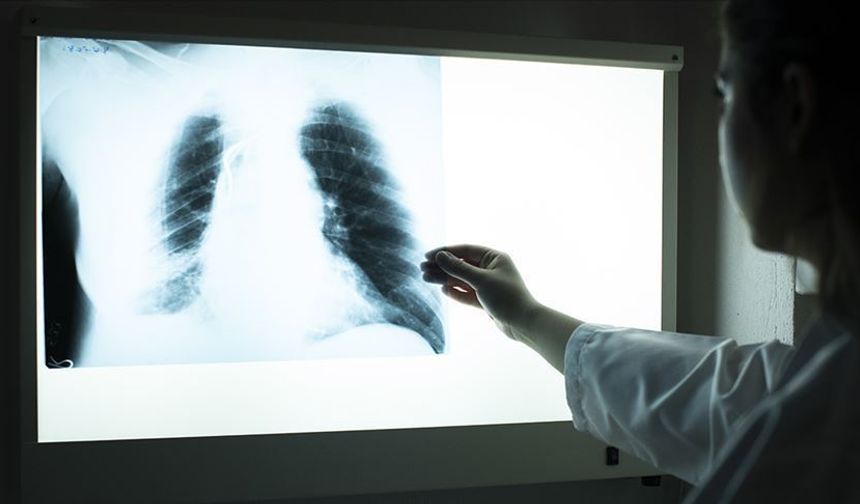

Obezite kanser riskini artırıyor